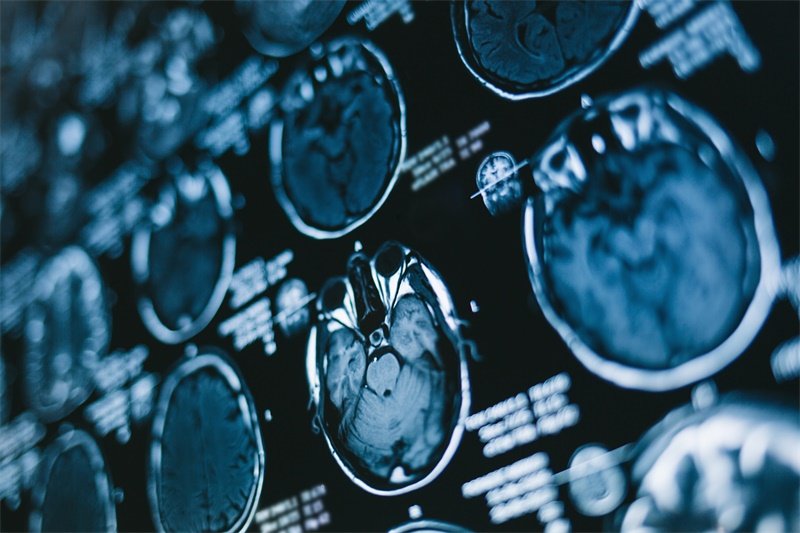

影像学检查

磁共振成像(MRI)和计算机断层扫描(CT)是最常用的影像学检查方法,其能够帮助医生准确判断病变的性质及范围。

对于恶性病变,CT与MRI也有助于观察肿瘤的侵犯情况,为手术规划提供依据。